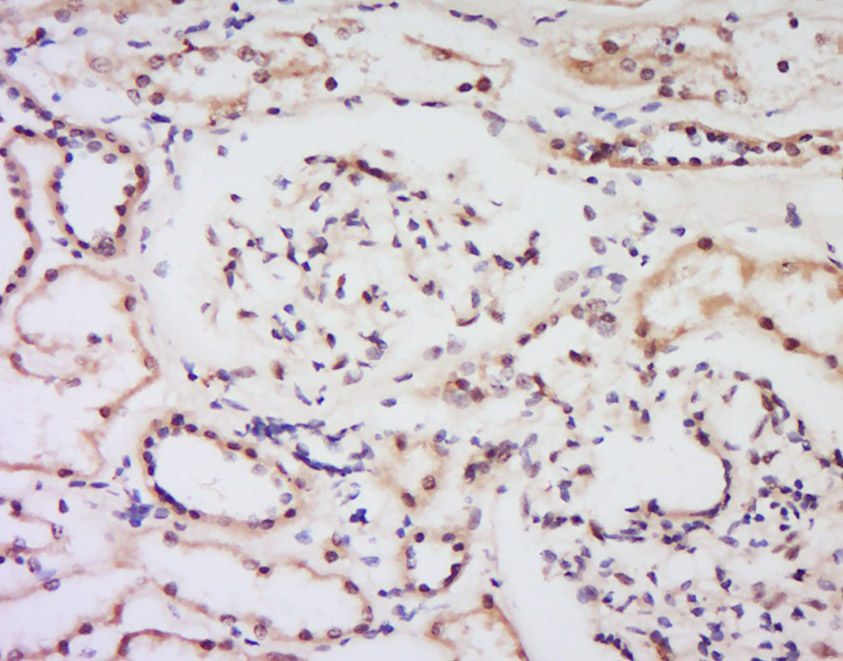

Tissue/cell: Human kidney tissue; 4% Paraformaldehyde-fixed and paraffin-embedded; Antigen retrieval: citrate buffer ( 0.01M, pH 6.0 ), Boiling bathing for 15min; Block endogenous peroxidase by 3% Hydrogen peroxide for 30min; Blocking buffer (normal goat serum,C-0005) at 37℃ for 20 min; Incubation: Anti-Bcl-2 Polyclonal Antibody, Unconjugated(bs-15533R) 1:200, overnight at 4°C, followed by conjugation to the secondary antibody(SP-0023) and DAB(C-0010) staining